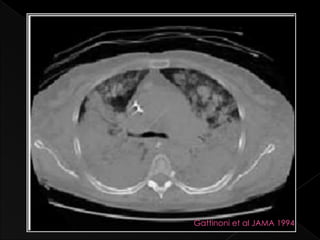

   Alveolar collapse

› Superimposed pressure on the lung

› Cephalad shift of diaphragm

 Diffuse lung consolidation, multifocal patchy

involvement and lobar or segmental disease

 Primarily in DEPENDANT lung regions

Gattinoni et al JAMA 1994

Alveolar collapse › Superimposed pressure on the lung › Cephalad shift of diaphragm  Diffuse lung consolidation, multifocal patchy involvement and lobar or segmental disease  Primarily in DEPENDANT lung regions › Ventilation and perfusion are no longer matched › Severe arterial hypoxaemia

Gattinoni et alJAMA 1994